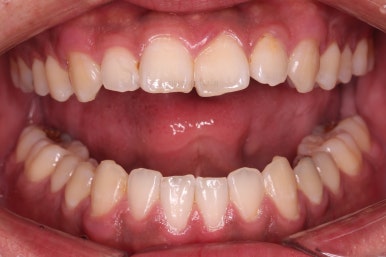

가지런한 느낌, 앞니 뻐드러짐을 좋게 했고요.

교합도 맞춰 위아래가 톱니바퀴처럼 맞물리게 했고, 앞니도 위아래 관계를 잘 맞추고 마무리를 했습니다.

전후 비교해 볼게요.

1년 3개월이라는 비교적 짧은 기간안에 적절한 교합, 심미성 등 여러 가지를 달성했던 만족스러운 치료였습니다.